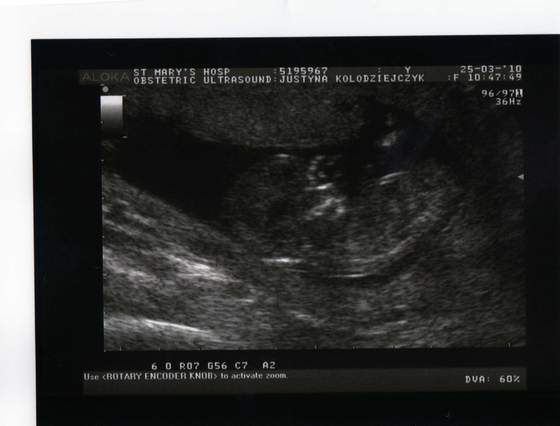

A to moje dzieciątko 11t3d, leży główką do dołu więc obróciłam zdjęcie bo tak lepiej się patrzy:

Kopia Zdjęcia z t&#.jpg